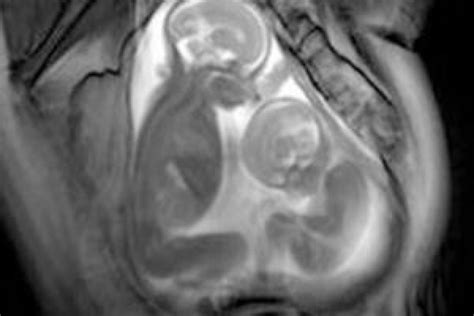

- Foto dell'Ecografia Creativa: Molti futuri genitori amano usare la loro prima foto dell'ecografia per rivelare la notizia. Per un'idea classica, tenete due foto dell'ecografia sopra la pancia.